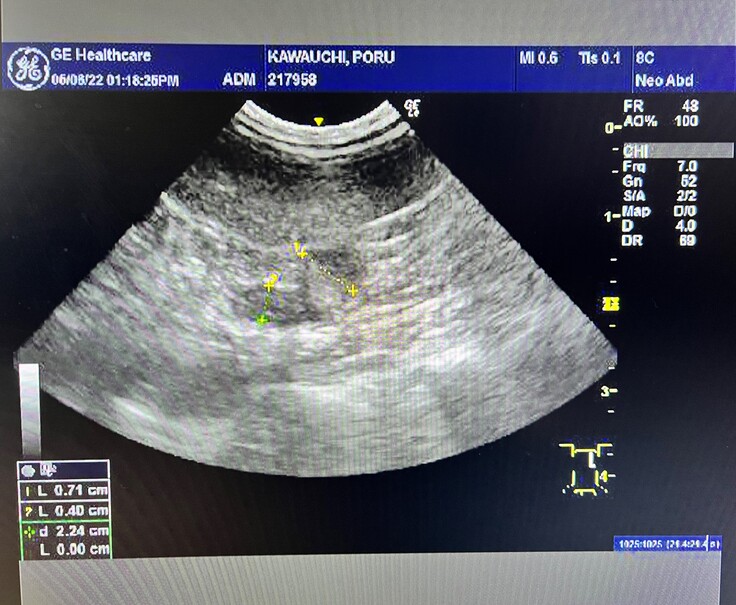

ポールに元気がない事に気がつき、食欲もないから4月8日にいつも行く動物病院に連れて行きました。

通常の健診と血液検査と超音波の結果、腎臓には異常な数値、石ができている事が発見。

肝臓の数値が通常の20倍で大きな塊が肝臓に発覚。

肝臓癌の可能性があると診断されました。

かかりつけの病院での超音波

↓掲載許可を得ています